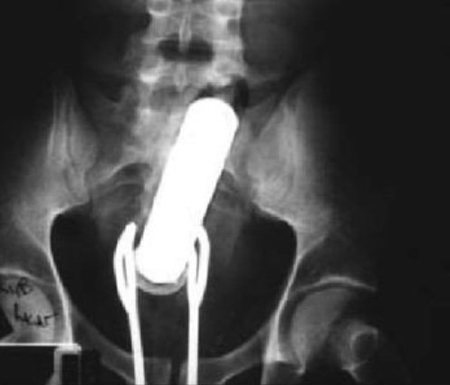

15. A Lightbulb Moment

How you may wonder, do you get a lightbulb stuck in your large intestine? A doctor from Pakistan removed the item from a prisoner. Now, you'd think this would be a memorable moment for him. But, he was totally just as baffled as everybody else as to how and why it was there.Advertisement